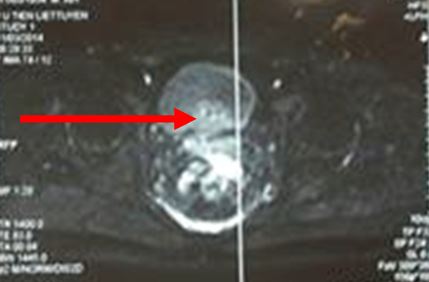

Hình ảnh MRI: khối u tuyến tiền liệt ranh giới không rõ, ngấm thuốc sau tiêm, kích thước 12 x 15 mm, chưa xâm lấn vỏ bao và túi tinh

Trước điều trị: tiểu són, tiểu nhiều lần; trên cộng hưởng từ khối u kích thước 12 x 15 mm, ranh giới không rõ, chưa xâm lấn vỏ bao và túi tinh; PSA = 2,4 ng/ml

Sau điều trị 7 tháng: thể trạng tốt, đi tiểu bình thường; trên hình ảnh cộng hưởng từ không có khối bất thường; PSA giảm xuống còn 0,26 ng/ml